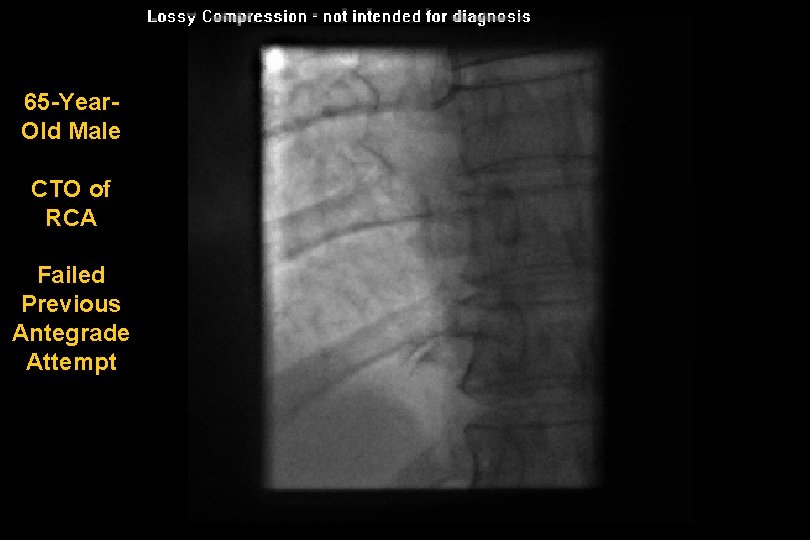

65 -Year. Old Male CTO of RCA Failed Previous Antegrade Attempt